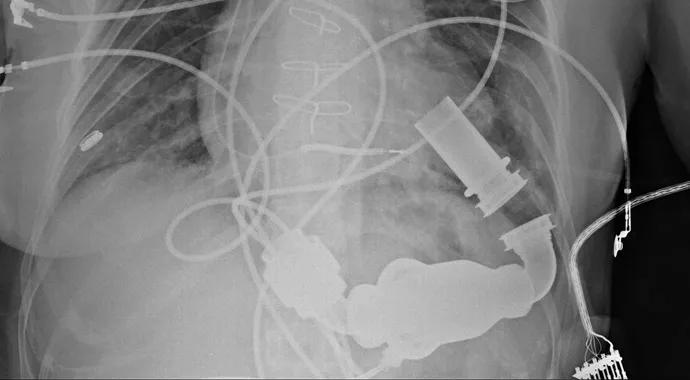

Topics featured at the 31st annual conference included interventional cardiology, cardiovascular medicine, cardiovascular surgery, thoracic surgery, transplantation and mechanical assist devices.

Conference attendees came from 20 states to hear about new approaches to valve repair and replacement, the use of cardiac assist devices, advances in vascular and cardiac hybrid procedures and much more. “All these cutting-edge interventions require nurses and physicians working hand-in-hand to care for patients,” says Klein.